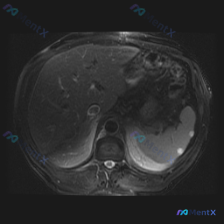

看到一份腹部MRI的读片资料,病灶在脾脏,整理一下思路分享给大家。 病例影像核心信息 - 影像类型:腹部MRI T2加权序列(T2WI),轴位 - 主要发现:脾脏边缘可见数个小类圆形高信号灶(点状高亮),呈水样信号,边界锐利、边缘光整 - 其他结构:肝实质信号相对均一,未见明确占位;胰腺体尾部形态、...

整理了一份很有意思的腹部影像病例,从单一病灶到全局判断,中间的思维路径值得复盘: --- 影像基础信息 - 序列:腹部MRI T2加权成像(T2WI)轴位 - 背景脂肪信号未抑制,为标准T2WI 关键影像表现 1. 脾脏病灶: - 位置:脾脏边缘(外侧) - 数量:2个类圆形结节 - 信号:T2WI...